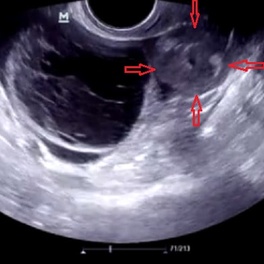

Воспаленная маточная труба, яичник: сальпингоофорит и его клиническая картина.